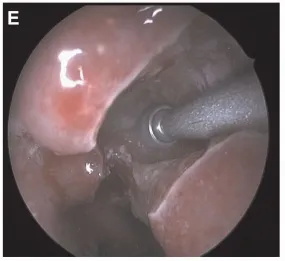

▼使用3mm高速弯曲金刚石钻头磨除下鼻甲(Midas Rex LegendR telescope,Medtronic,Dublin,Ireland)。在SS下方的上斜坡钻孔磨除骨质以暴露肿瘤(图E)。